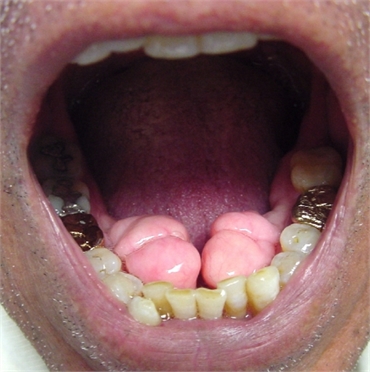

Approximately 7% to 10% of the U.S. population has this noticeable boney growth along the surface of the mandible nearest the tongue called Mandibular Tori (Torus Mandibularis). The condition often presents close to the premolars, just above where the mylohyoid muscle attaches to the mandible. It always occurs on the inner side of the patient’s lower jaw. Conversely a torus that appears on the midline of the palate is called a Torus Palatinus. In rarer causes torus can also appear on the cheek (buccal) side of both upper and lower jaws.

In 90% of cases mandibular torus (singular) or tori (plural) appear on both the right and left sides of lower jaw. The abnormality occurs spontaneously, with nothing patients can do to prevent it. Sometimes mandibular tori are large enough to touch each other at the mouth’s midline and size may fluctuate throughout the patient’s life.